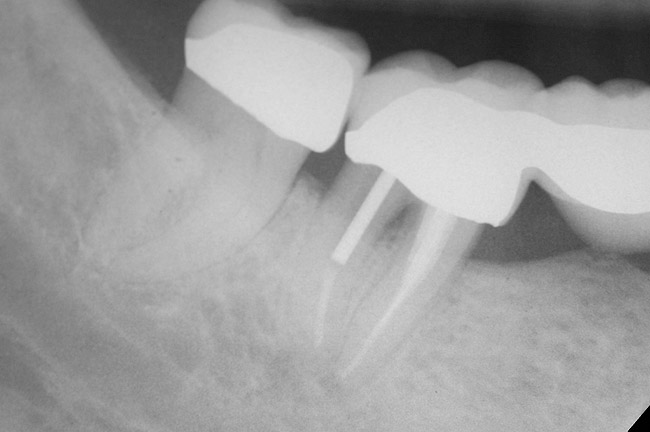

Figure 9  Extraction of teeth Nos. 29 and 31 with immediate implants (Straumann USA, Waltham, MA) placed into the site.

Figure 9

Figure 10  Implants seen in Figure 9 restored approximately 3 months after placement.

Figure 10